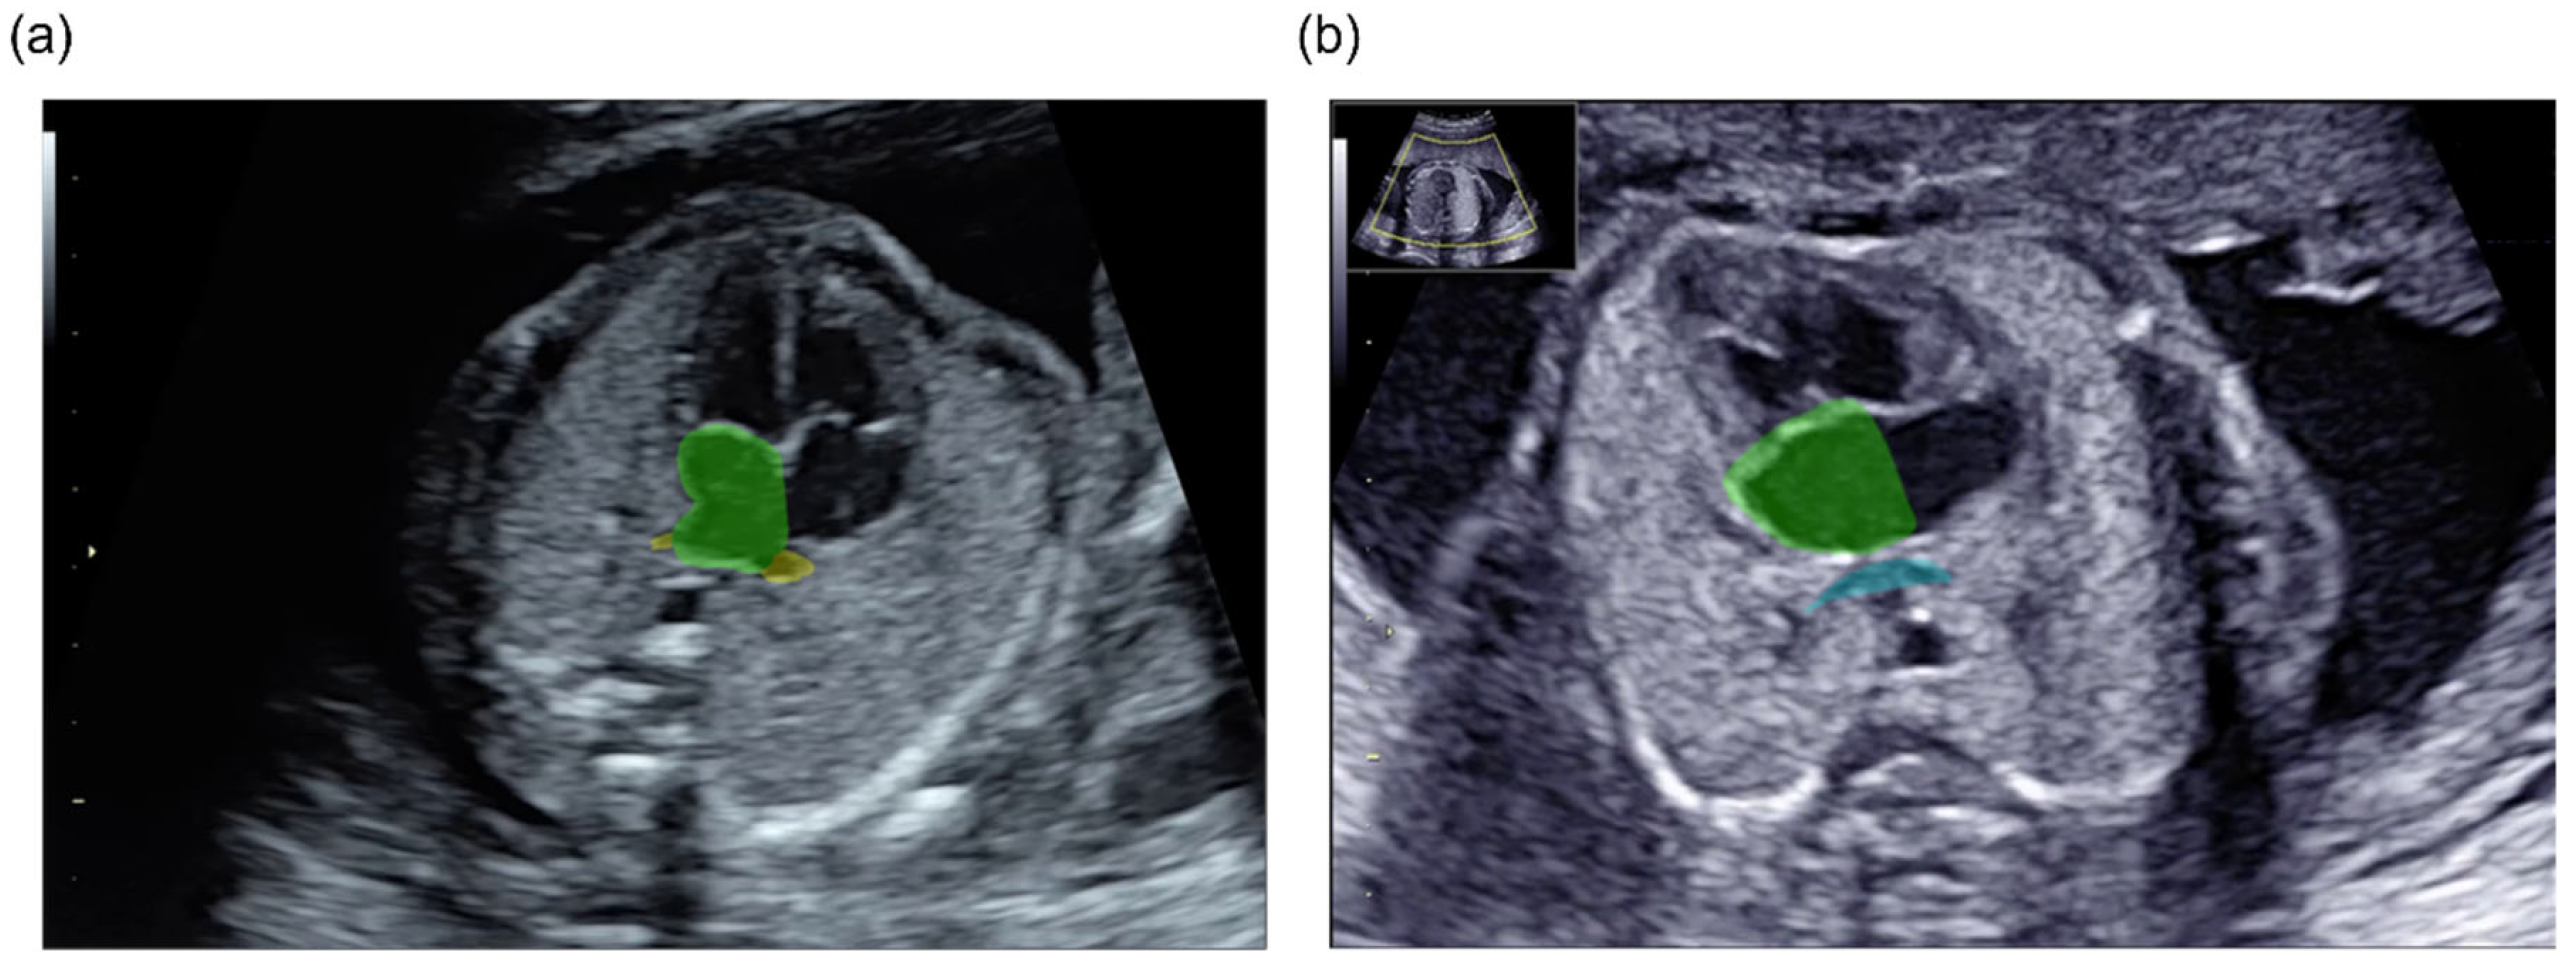

3.1. Three-Dimensional Visualization and Detection of the PV-LA Connection